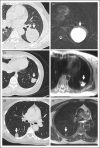

Pulmonary cystic echinococcosis

Purpose of review: The aim of our review is to summarize specific clinical, diagnostic and treatment aspects of pulmonary cystic echinococcosis. The lung is the organ second most affected by cystic echinococcosis with approximately a quarter of cystic echinococcosis cysts. Most cysts are in the liver. Apart from the watch and wait approach for selected inactive cysts [cystic echinococcosis CE4, CE5], the well established WHO cystic echinococcosis cyst classification-based treatment of hepatic cystic echinococcosis cannot be applied to pulmonary cystic echinococcosis cysts. Some standard interventions can even be harmful when applied to pulmonary cystic echinococcosis cysts.

Summary: Surgery is the mainstay of treatment for pulmonary cystic echinococcosis cysts. Parenchyma-sparing surgical techniques should be used whenever possible. Albendazole induces decay of the parasitic cyst membrane, opening of cystobronchial fistulas and cyst complications, which can be life threatening. It is strongly recommended to seek advice from expert centres, including differential diagnoses, treatment and a long-term management plan.